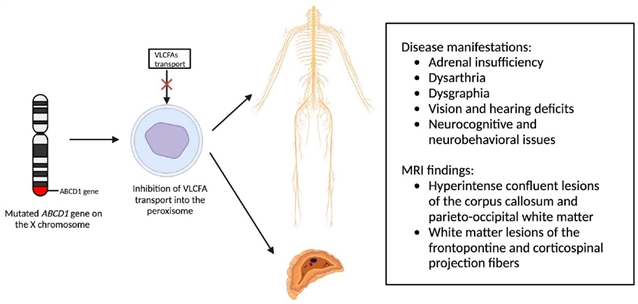

1. X - 连锁肾上腺脑白质营养不良(最常见)

由 X 染色体 ABCD1 基因突变导致极长链脂肪酸异常蓄积,主要累及男性。

• MRI 特征:胼胝体与顶枕部白质出现融合性高信号病灶,伴随钆增强强化,疾病后期可累及全脑白质;脊髓 MRI 可见皮质脊髓束与后柱变性。

• 辅助检查:血液极长链脂肪酸水平升高,新生儿筛查可早期发现。

X 连锁肾上腺脑白质营养不良的病理生理学机制:X 染色体上 ABCD1基因发生突变,导致极长链脂肪酸(VLCFAs)无法进入过氧化物酶体,进而因极长链脂肪酸在全身蓄积引发相应临床表型。